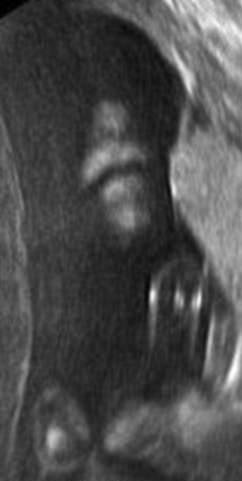

▼这个宝宝则在打自己的脸,他的动作从超音波照片中看得一清二楚。

▼怀孕7个月的準妈妈去做超音波检查,发现宝宝伸出了两根手指。